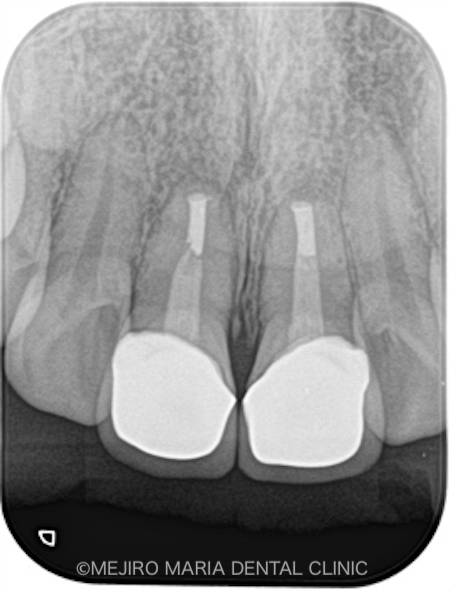

|術前レントゲン画像_治療後1-1.png)

|術直後レントゲン画像_治療後2-1.png)

|術後レントゲン画像_治療後3.png)

術後2週間で、術野の腫脹はほぼ消えて、術前に見られていた瘻孔(フィステル)の消失も確認できました。

3ヶ月後には瘻孔(フィステル)と、術前に訴えていた違和感は消失し、術野の歯肉の治癒も良好であることを確認しました。レントゲンでも、根尖部付近の骨の再生が認められたため、予後良好と判断しています。